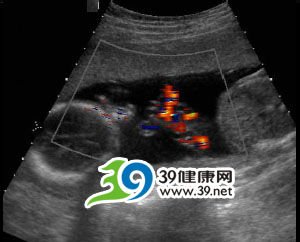

出现脐带缠绕时,产前可以通过B超检查胎儿身体上有无脐带压迹确诊,有经验的B超医师可以准确地测出脐带缠绕的周数。检查缠绕是否影响到胎儿健康,可以通过胎儿电子监护观察胎儿心率的变化,如果出现胎心不规则的减速或变异幅度过大时,就应考虑是脐带受到牵拉、挤压。

现在大多通过产前B超检查就可确诊。目前对于这种异常没有治疗方法,应密切注意胎儿的状况,如果胎儿一直没有缺血、缺氧出现,就可以继续怀孕,直至分娩。